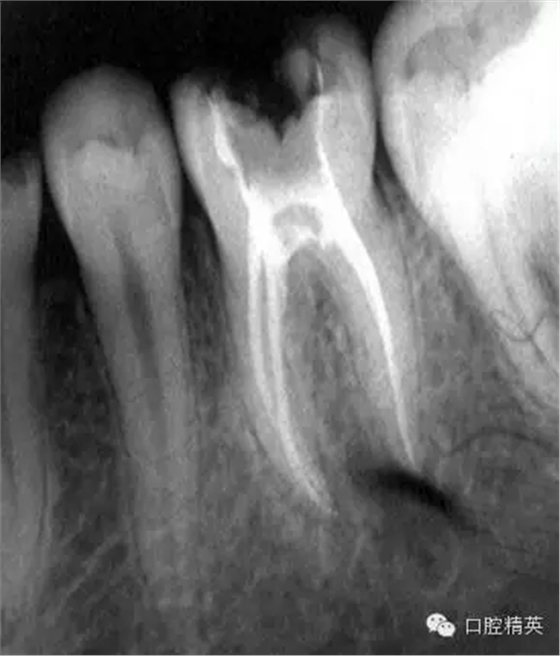

三 根管充填:

1,冷牙膠充填:選擇主尖進(jìn)行試尖,插入主牙膠尖后到達(dá)工作長度感覺根尖強(qiáng)烈摩擦感方為合適,采用螺旋輸送器輸入糊劑,插入主尖依次采用由大到小的測壓器進(jìn)行測壓,嚴(yán)密根充。

2熱牙膠充填,選擇主尖,試尖,標(biāo)準(zhǔn)和冷牙膠相同,不用螺旋輸送器進(jìn)行糊劑輸送。只蘸取少量糊劑與主尖上插入根管,因為糊劑過多可能在切斷主牙膠時將牙膠帶出或帶松,采用攜熱器燙斷多余牙膠尖,燙斷后攜熱器不加熱下停留10秒,防止主牙膠加熱膨脹,余留根尖部牙膠長度約2-4mm,分層注入熱牙膠,垂直嚴(yán)密加壓。